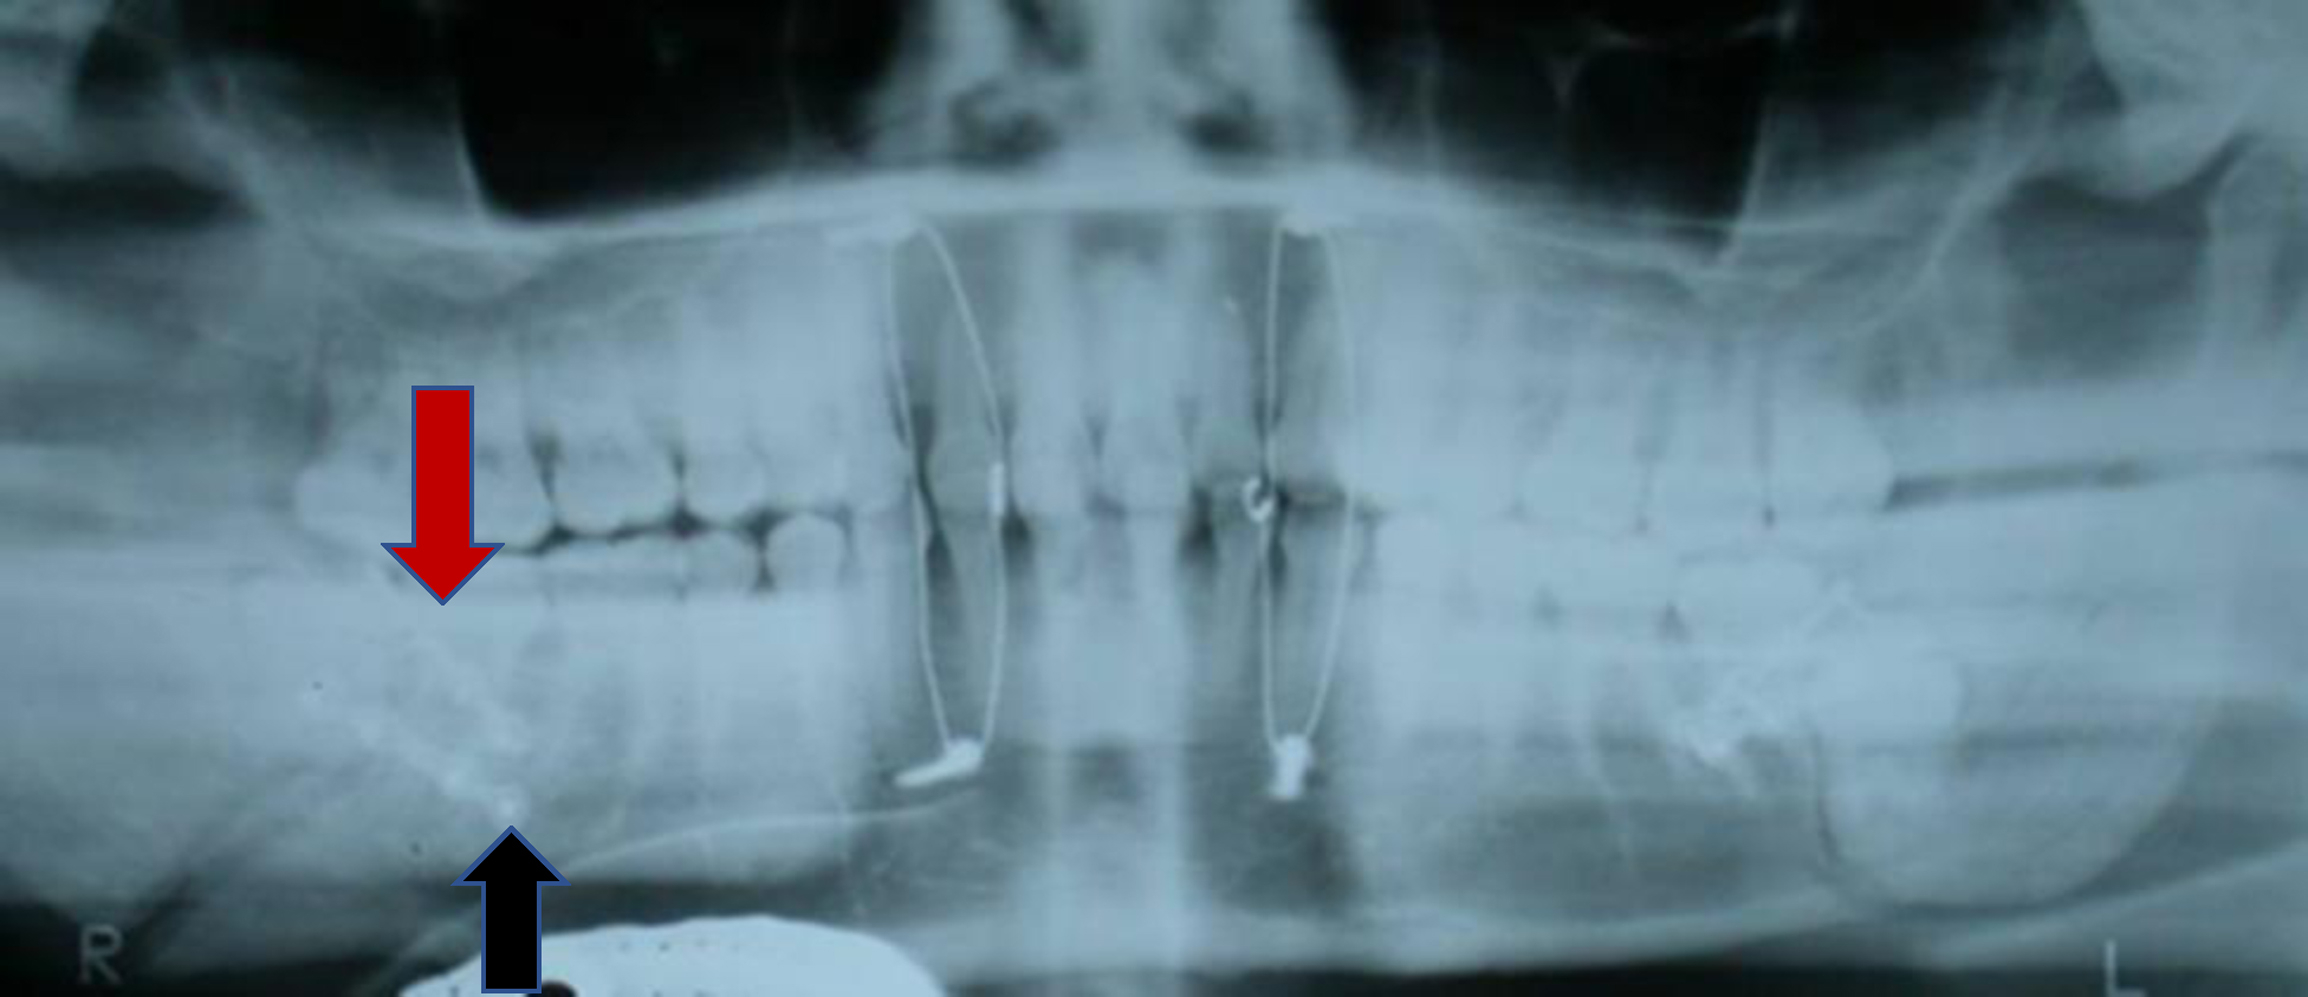

Once a mandible fracture is suspected based on history and physical examination, there are several diagnostic imaging modalities that can be used based on availability. Panorex plain films (orthopantomogram) in combination with a posterior-anterior plain film will provide two views of the mandible which would show an MAF, while a panorex radiograph alone may miss a posterior fracture. However, the equipment to obtain panorex views tends to be of limited availability in the hospital-based emergency room setting, and thus, a mandible series of radiographs or CT have been adopted as the gold standard. A mandible series includes three views: posteroanterior, oblique, and lateral. However, these three views may not clearly visualize the condyles. CT imaging has become the modality of choice and has been shown to have a 100% sensitivity to detect all fractures of the mandible. CT also has the advantage of assessing the involvement of tooth roots in the line of fracture, the presence of severe dental disease, and also screens for other facial fractures. Additionally, CT scans can be used to produce three-dimensional reconstruction which can help with operative planning or the selection of patient-specific plating if necessary.

There have been numerous studies investigating the use of one versus two monocortical miniplates in open reduction and internal fixation of MAFs. Historically Michelet and colleagues, and later Champy and colleagues, introduced of the use of a single miniplate on the superior lateral border of the mandibular angle for osteosynthesis in MAFs ( Fig. 4 ). However, given the tensile forces of elevation on the mandibular ramus countered by the depressor forces on the mandibular body, later studies theorized that two miniplates should be placed, one superior and one inferior across the MAF ( Fig. 5 ). This has not been borne out in the literature as studies in which two points of fixation were used had higher complication rates than studies in which one miniplate was used. , A 2014 systematic review and meta-analysis by Al-Moraissi and Ellis found the use of one miniplate to be superior to the use of two, reducing postoperative complications (including dehiscence, infection, nonunion, malunion, malocclusion, and hardware failure). This corroborated randomized control trials of the same topic, showing that the use of two miniplates for MAF gave no additional benefit and increased both procedure time and risk of postoperative complication.